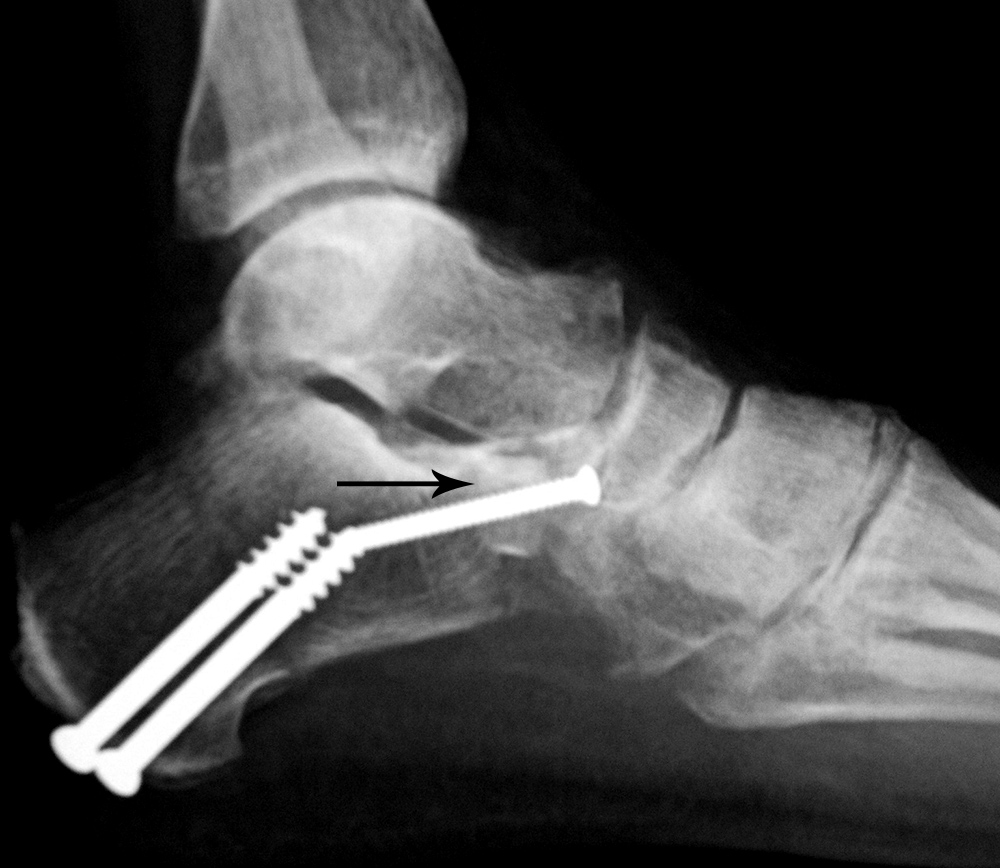

Calcaneal autogenous bone graft

Calcaneal autogenous bone plug

46 year-old man with posterior tibial tendon tear, Achilles tendon contracture, and planovalgus foot alignment. He was treated with Achilles tendon reattachment and two large partially threaded cancellous bone screws stabilizing a mid-calcaneal osteotomy. In the anterior portion of the calcaneus there is an autogenous iliac crest bone plug (arrow) stabilized by a fully threaded cortical bone screw.